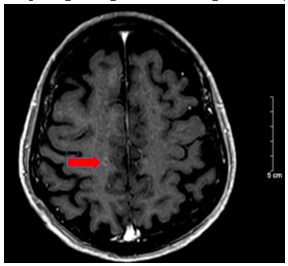

- Chụp cộng hưởng từ sọ não tháng 10/2024 (trước điều trị)

Hình 2:

Vỏ não thùy trán hai bên và thùy đỉnh phải có các nốt tăng ngấm thuốc sau tiêm, nốt lớn nhất ~ 4mm (mũi tên đỏ) – Theo dõi thứ phát